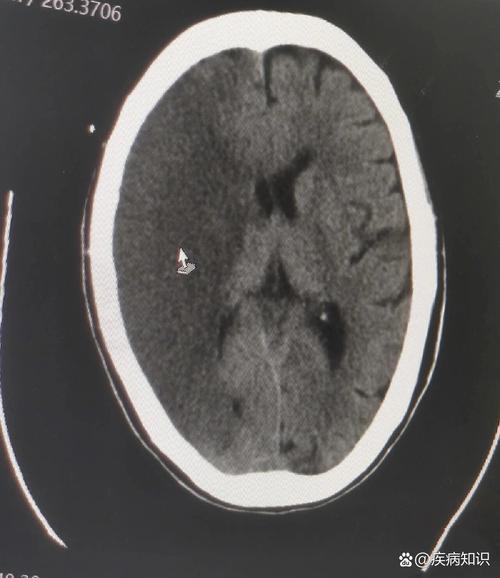

轻微脑梗 (Minor Stroke) - 医学术语:腔隙性脑梗死 或 脑小血管病

- 它是什么? “轻微脑梗”通常不是指那种导致严重偏瘫、失语的大面积脑梗,而更多是指“腔隙性脑梗”,它是由大脑深部的一些非常细小的穿通动脉被堵塞引起的,梗死的范围很小,像个小“腔隙”。

- 您的发现: “轻微脑梗”的存在,比单纯的“斑块”更进一步,表明脑损伤已经发生,这强烈提示需要立即进行全面的评估和干预,以防止未来发生更严重的、致残性的中风。